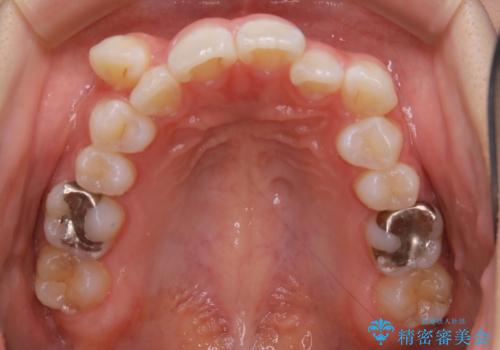

ガタつきがあるだけでなく、元々永久歯が欠損している「先天欠如」で歯の本数が少なく噛み合わせ等も治療する必要がありました。

稀に、乳歯が抜けてもその後に永久歯が生えてこないことがあります。生まれつき歯の元となる「歯胚」というものが欠如していることが原因で本数が少なることを「先天欠如」といいます。

こういったケースの治療では欠損している歯の本数分反対の顎の歯(上顎に欠損がある場合は下顎の歯)を抜歯してスペースの調整をする場合や、欠損歯の幅分のIPRを反対の顎の歯に設定することでスペースのコントロールをするという方法、欠損している歯の分のスペースを残して矯正を終了し最後にブリッジ治療やインプラントで歯の本数を増やすという方法があり、状況や患者さんの希望により選択をしていきます。